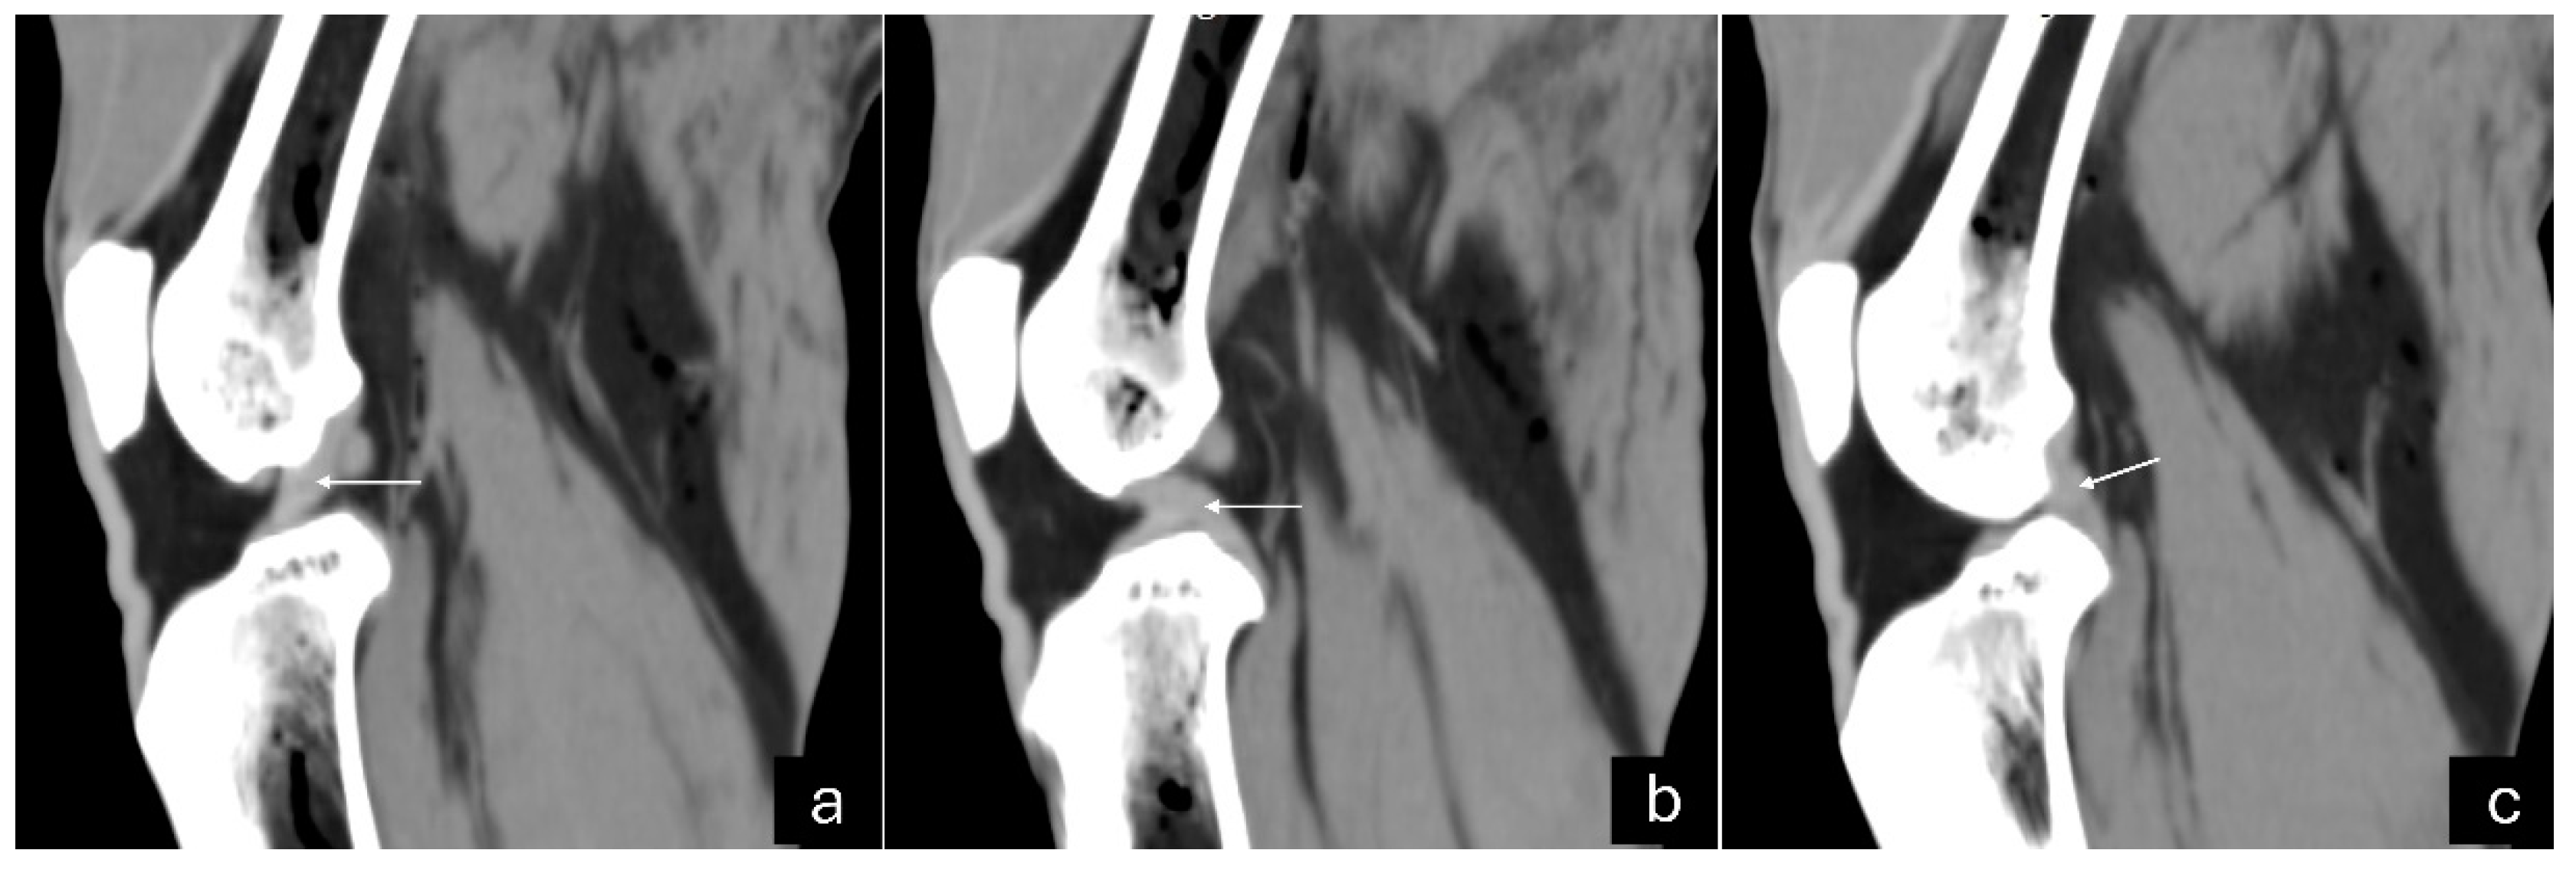

Figure 3. Sagittal computed tomography images on sagittal plane of an adult puma stifle joint (Puma concolor). (a) Cranial cruciate ligament. (b) Caudal cruciate ligament. (c) Meniscofemoral ligament.

The 3D reconstruction of CT images (Figure 2c) revealed, in a cranial view, the patella as a raindrop-shaped structure with a wider base than the apex, positioned in the symmetrical trochlear groove. Meniscal mineralization was identified in the stifles of the same four animals as a hyperdense portion in the medial compartment. The caudal and lateral views displayed the lateral and medial fabellae in the epicondylar region of the lateral and medial condyles, respectively, with the lateral one being larger (Figure 2d). Other bone structures showed similar patterns as seen in radiographic images. Multiplanar and cross-sectional images allowed identification of the patella, infrapatellar fat, cranial cruciate ligament (from the caudal portion of the femur to the cranial area of the tibia), caudal cruciate ligament (from the cranial aspect of the femur to the popliteal margin of the tibia) and meniscofemoral ligament (Figure 3). The menisci were more difficult to identify, but those with partial mineralization were easily visualized (Figure 4). The fabellae and sesamoid of the popliteal were also identified; all had a thin cortical layer.